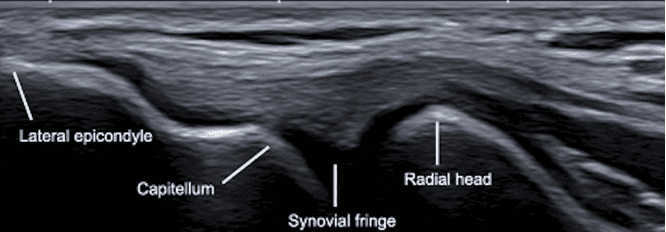

Key Landmarks

- Lateral Epicondyle: Visualized as a hyperechoic cortical surface, serving as the bony attachment site for extensor tendons.

- Common Extensor Tendon: Appears as a fibrillar, hyperechoic structure originating from the lateral epicondyle.

- Radial Head: Evaluate for joint effusion or other abnormalities proximally.